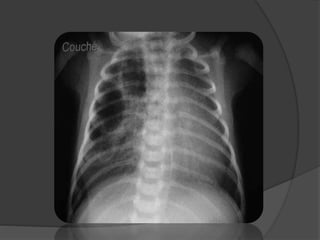

IMAGERIE:

LA RADIOGRAPHIE DU THORAX

 Opacité généralement lobaire inférieure,

+++ G, bien limitée homogène pouvant être

le siège d’un niveau hydro-aérique

 Arrondie → SIL / Triangulaire → SEL

 Artère systémique:

rarement visualisée.

image basithoracique interne tubulée,

homolatérale.